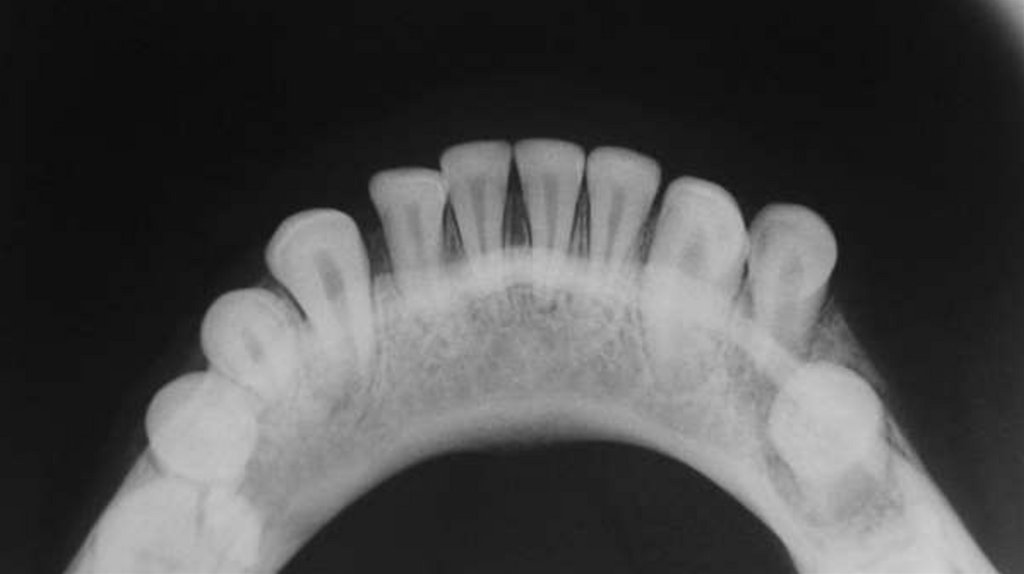

Были собраны подробные истории болезни, проведены

клинические и рентгенографические исследования, такие как

ортопантомография, окклюзионная рентгенография и

внутриротовая периапикальная рентгенография . После

тщательной оценки был поставлен диагноз типа перелома и был

составлен план лечения для каждого пациента.

Послеоперационные рентгенограммы были получены для

подтверждения заживления места перелома перед удалением

шины (рис. 5 и рис. 8), и все пациенты наблюдались в течение 12